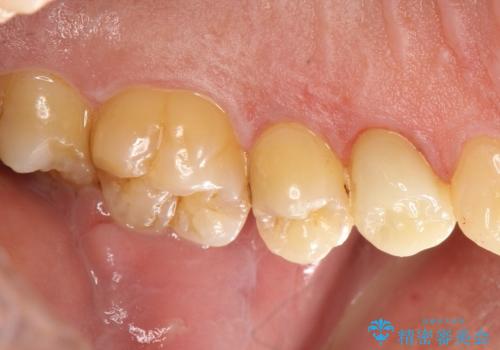

大きな虫歯で崩壊した歯の修復

虫歯で奥歯が真っ黒になり崩壊していましたが、悪い部分を完全に取り除き、丁寧に修復することでまた長く機能させることができます。

かぶせ物のの種類:Bellezza